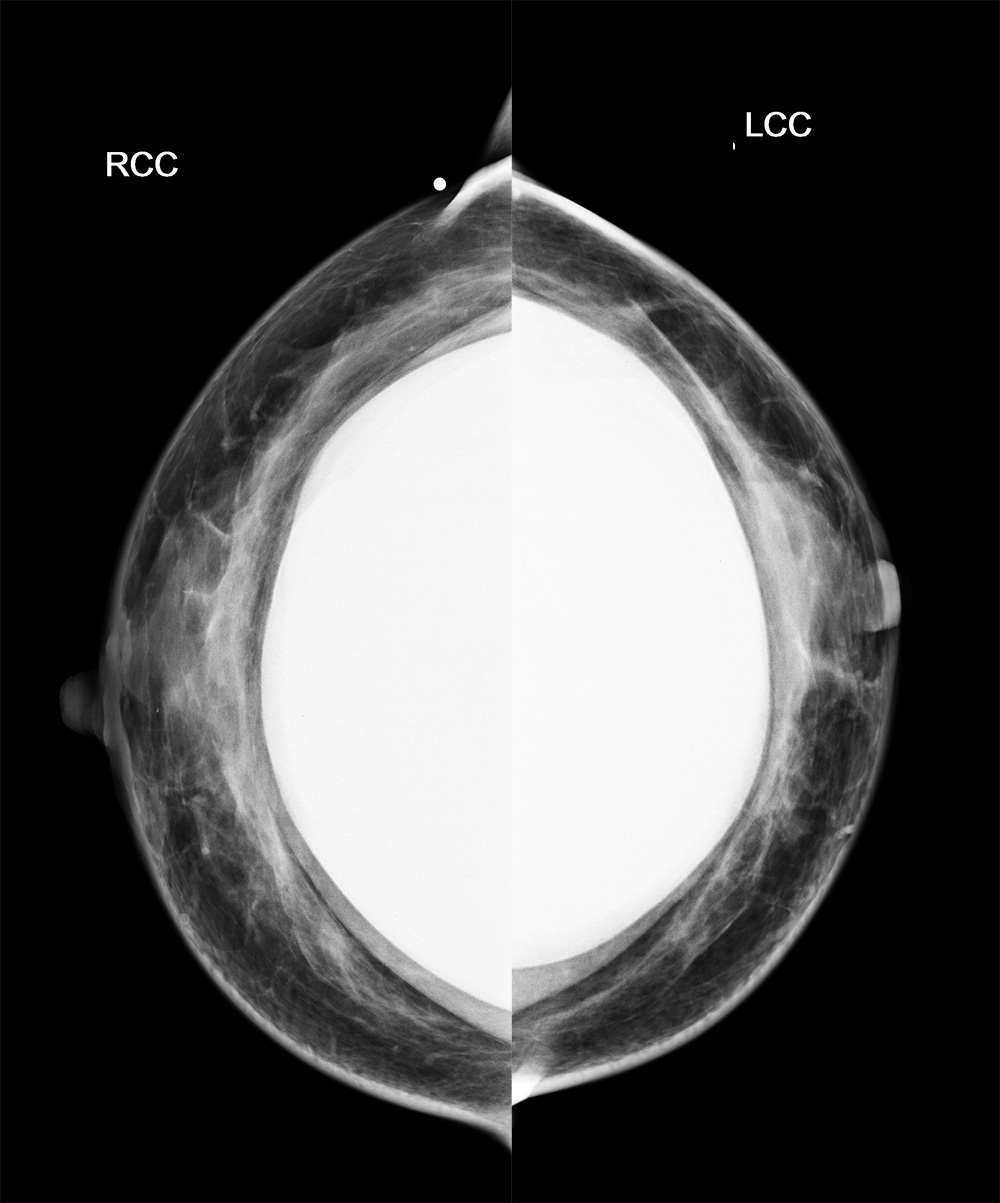

◂Breast Anatomy